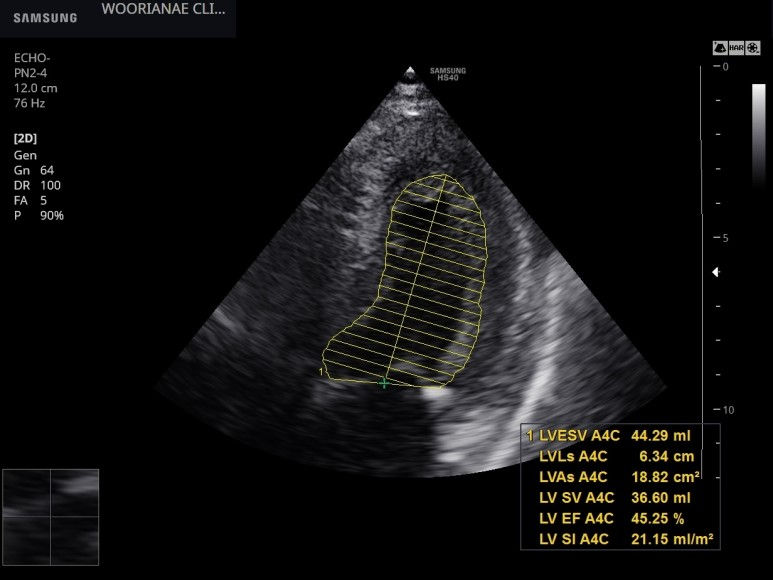

4일뒤 심장 초음파 시행

이완기 기능 E/e` 11.7, 감소한 e`, s`에서 심장의 길이방향의 움직임이 둔해진 것을 확인할 수 있다.

좌심방은 확장되지 않았다.

수축기 기능은 여러번의 측정에 40~45% 범위, 경도~중등도로 감소되어 있다.

심실벽 운동은 대칭적으로 전반적인 움직임 감소